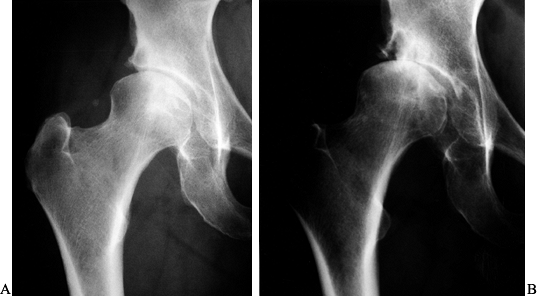

Figure 104.2. A:

AP radiograph of the left hip in a healthy and active 52-year-old woman with a 4-year history of hip pain. Periacetabular osteotomy was discussed as the probable treatment of choice. B: This AP radiograph taken 7 months later showed rapid progression of the arthritis, requiring cancellation of the osteotomy that was planned. |

Figure 104.3. AP radiograph of the right hip (A) and a false profile view (B) of a 43-year-old woman with right hip pain and moderately advanced arthrosis. A periacetabular osteotomy is seen on the AP (C) and false-profile views (D).

The patient had a delayed union of the pubis, but by 8 months after surgery she was asymptomatic and back to full activity with no limp. |